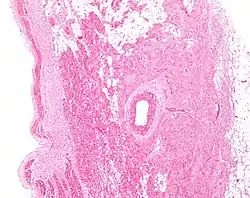

Microanatomy

The cells of the SA node are spread out within a mesh of connective tissue, containing nerves, blood vessels, collagen and fat. Immediately surrounding the SA node cells are paranodal cells.[2] These cells have structures intermediate between that of the SA node cells and the rest of the atrium.[6] The connective tissue, along with the paranodal cells, insulate the SA node from the rest of the atrium, preventing the electrical activity of the atrial cells from affecting the SA node cells.[2] The SA node cells are smaller and paler than the surrounding atrial cells, with the average cell being around 8 micrometers in diameter and 20-30 micrometers in length (1 micrometer= 0.000001 meter).[7] Unlike the atrial cells, SA node cells contain fewer mitochondria and myofibers, as well as a smaller sarcoplasmic reticulum. This means that the SA node cells are less equipped to contract compared to the atrial and ventricular cells.[8]